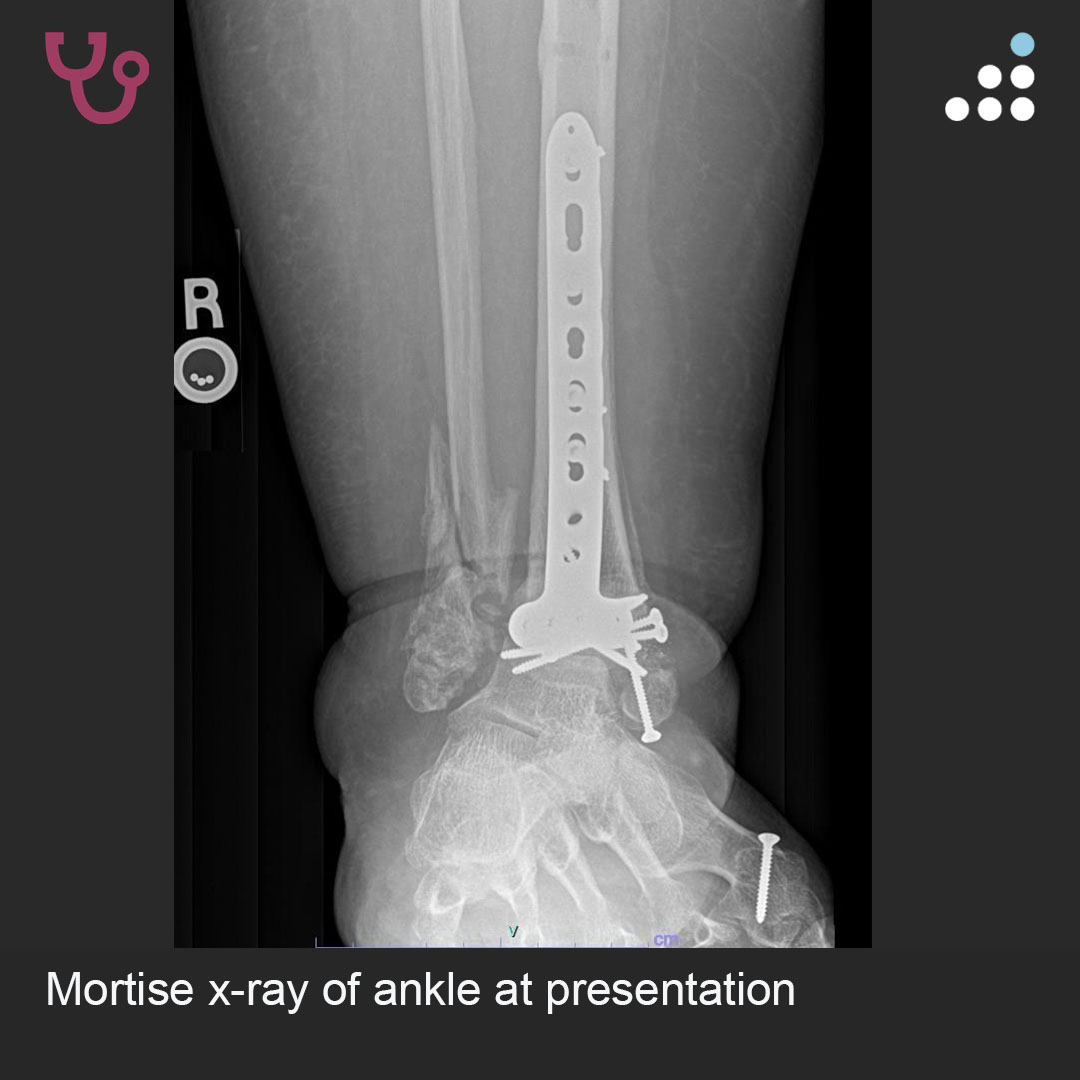

Here is a new case by Dr. Jan Szatkowski @orthotraumamd and @IU_Health.

PILON FRACTURE NONUNION IN 58F

How would you manage this #orthotwitter?

Vote on this case for CME: orthobullets.tiny.us/2a9tbyyj

@orthobullets @IU_Health @bonesmith_ @DrFraneNicholas @KrystinHiddenMD @FractureDoc @itius @rkh_md @BrandonYuanMD @IMNailR @schulte_ss @Drlyndonmason What would be your plan here? @rkh_md @FootAndAnkleMD @IMNailR